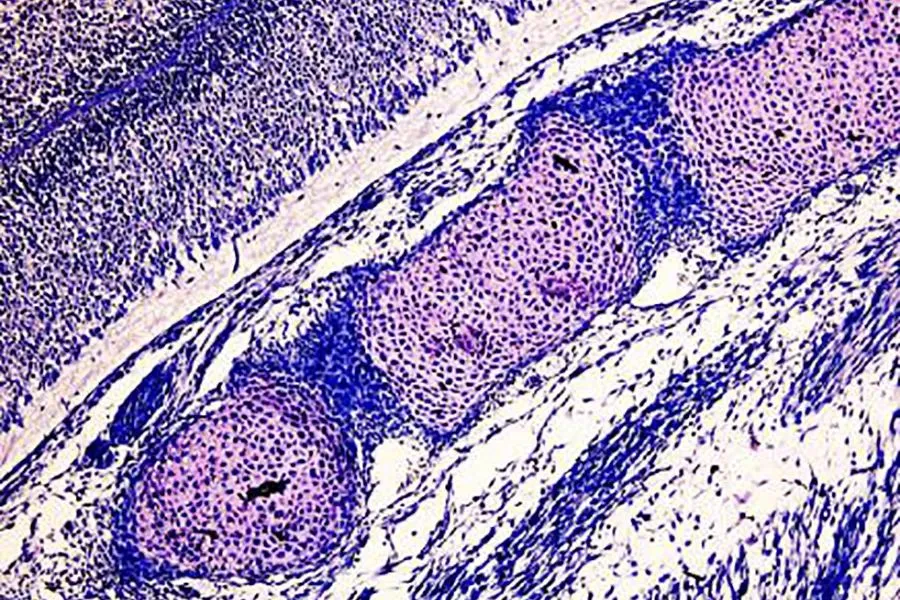

图片

Masson三色染色试剂盒-正常小鼠肾组织